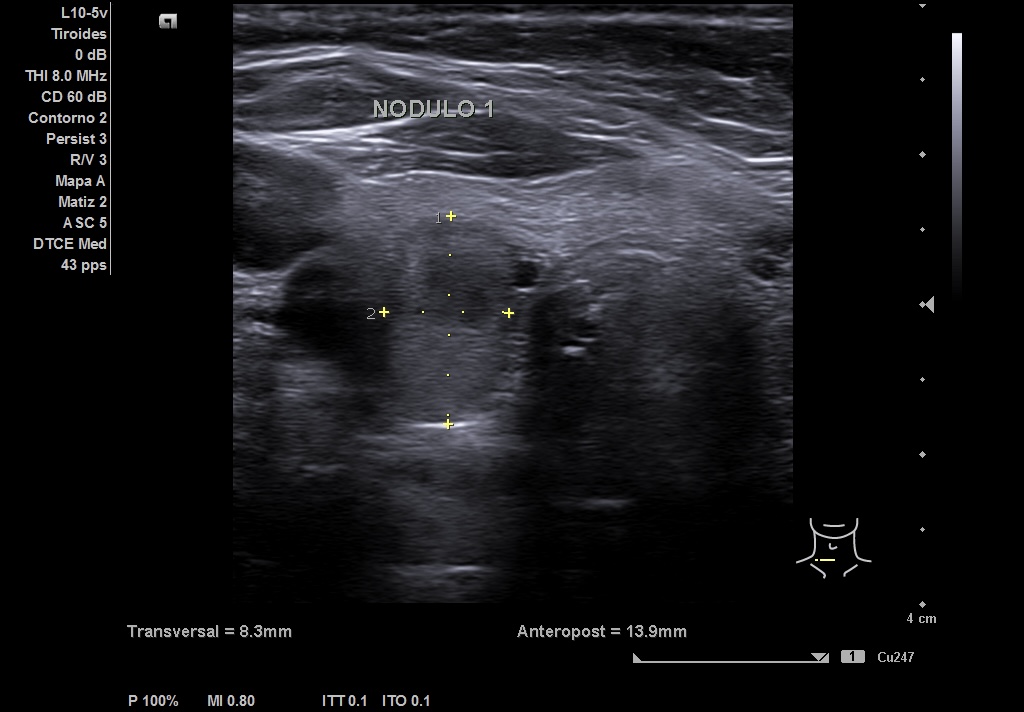

Se realiza ecografía en el Centro de Salud, en la que se objetiva en LTD un nódulo que impresiona de bilobulado, sólido, con una región caudal calcificada que no deja valorar su contenido y una parte superior isoecoica con alguna zona más hipoecoica. Diámetro antero-posterior (13 mm) mayor que el transversal (8 mm) y sagital (19 mm). Vascularización periférica. TIRADS 4-5.